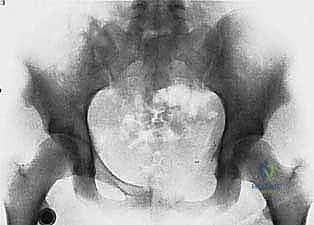

5. Reconstruction

"With the tumor resected, we now face the challenge of reconstruction. The goal is to restore stability and function. For this extensive periacetabular defect, we have several options."

- Options: "We could consider a custom 3D-printed endoprosthesis, an allograft-prosthesis composite, or even a saddle prosthesis. Given the patient's age and functional demands, we've opted for a custom endoprosthesis to reconstruct the acetabulum and restore continuity of the pelvic ring. This will be secured with multiple screws into the remaining ilium and ischium."